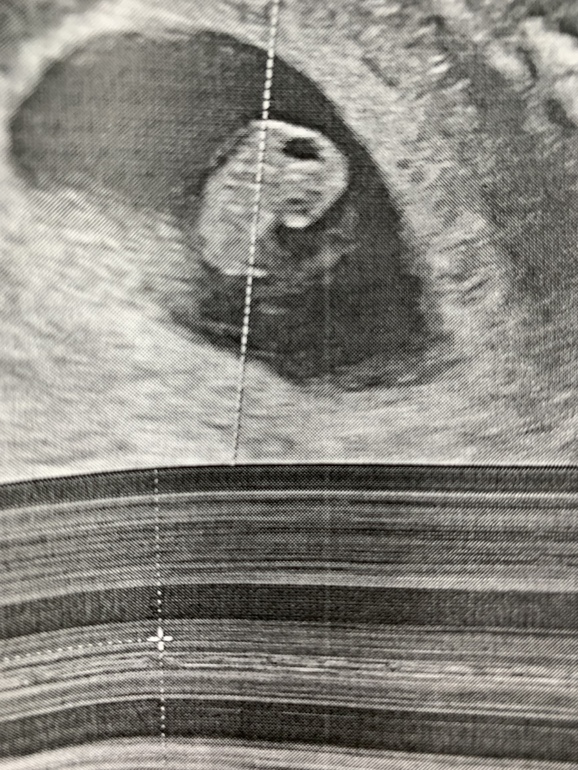

Узи 7,4 недели и постоянная мазня!

У меня очень похожая история, лежу из-за темной мазни вторую неделю в больнице с угрозой. Мне на третьем узи нашли все таки гематому маленькую 2 мм. Начинаю клексан с понедельника, побаиваюсь, как бы под его воздействием не закровило по-новой

Та вот у меня уже 4 узи аш ,за это время,ни кто из врачей не видит ни отслоек,ни гематом.Может все таки из-за предлежания?

да дело в том,что уже 3 специалиста смотрели,на разных аппаратах.Нет отслойки и все тут.Вот может действительно из-за предлежания?!!еще и клексан колю.